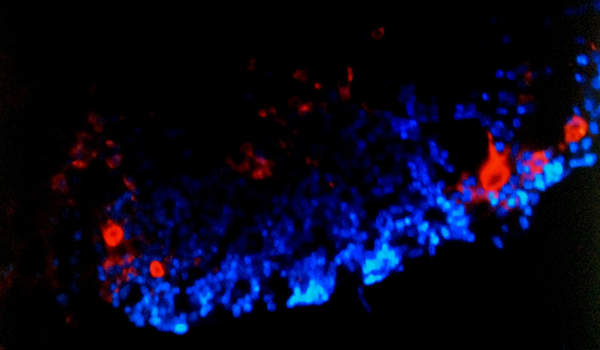

Cardiac stem cells, pictured here, give hope to patients who have suffered a heart attack.

The cells, known as Sca-1+ stem enriched in Islet (Isl-1) expressing cardiac precursors, play a major role in cardiac development. Until now, most of the research has focused on a different subset of cardiac progenitor, or early stage, cells known as, c-kit cells.

The Sca-1+ cells, like the c-kit cells, are located within a larger clump of cells called cardiospheres.

The UCSF researchers used special culture techniques and isolated Sca-1+ cells enriched in the Isl-1expressing cells, which are believed to be instrumental in the heart’s development. Since Isl-1 is expressed in the cell nucleus, it has been difficult to isolate them but the new technique enriches for this cell population.